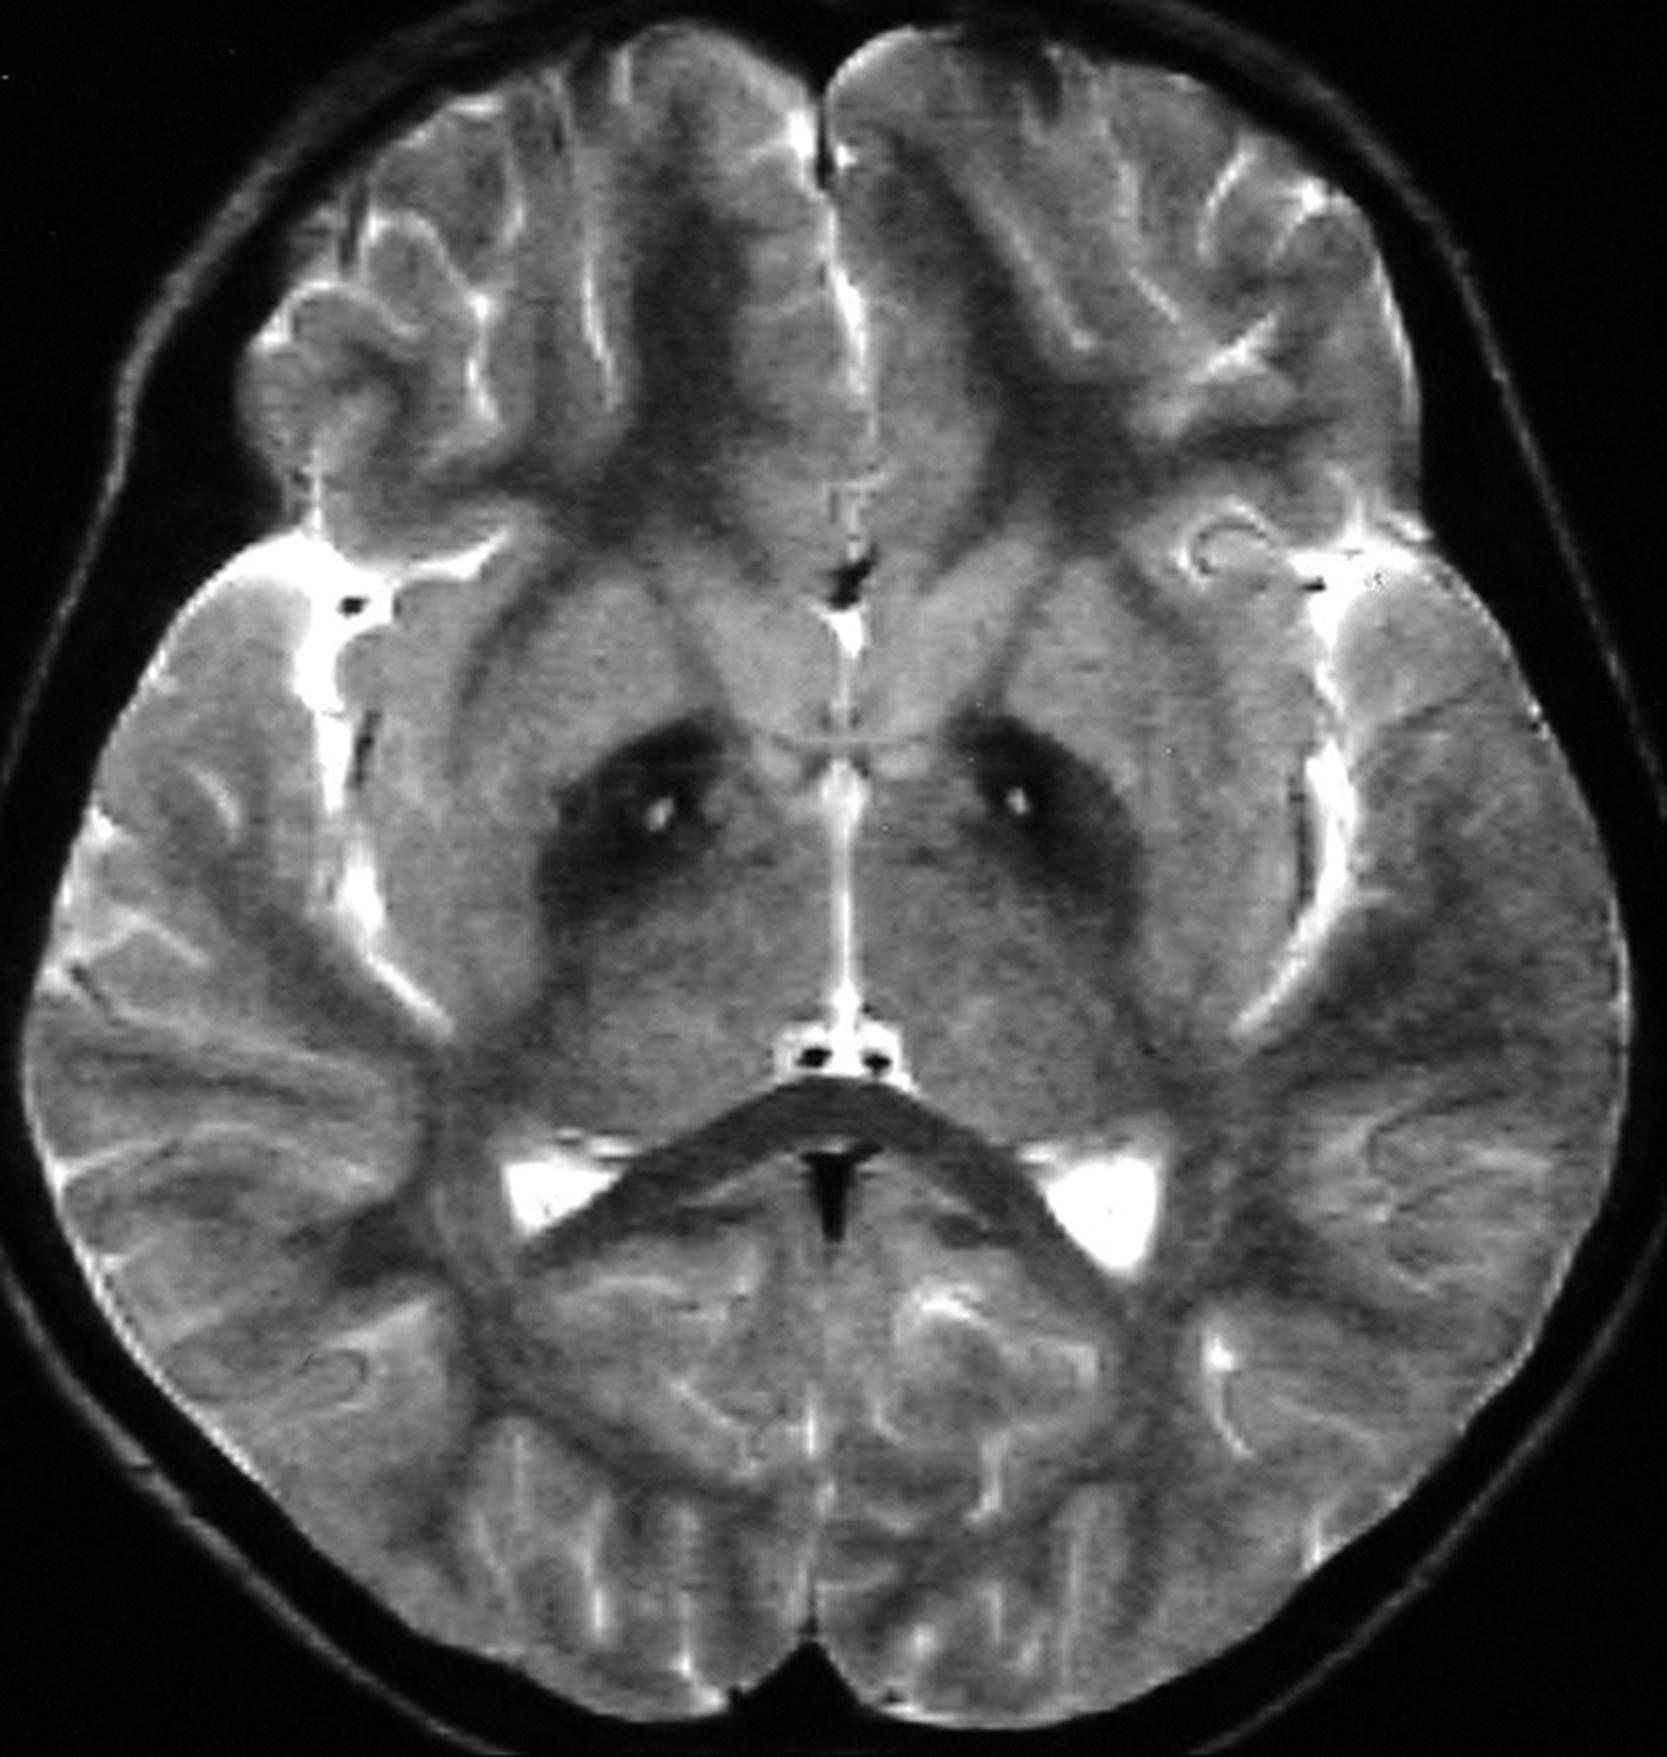

The diagnosis of PKAN depends on the presence of obligate features: onset in the first 2 decades, progressive course, extrapyramidal symptoms, and classic MRI findings showing hypointense T2-weighted and proton density signal in the globus pallidus and substantia nigra ( Fig. 17.6 ). The presence of a hyperintense area within the hypodense areas, named the “eye of the tiger sign,” is considered almost pathognomonic for PKAN. Hyperdense lesions may be present in presymptomatic patients, but as the disease progresses hypodensities appear and ultimately predominate. , In patients with PKAN, 7-Tesla imaging has identified elevated concentrations of iron in the globus pallidus, substantia nigra, and internal capsule; not seen in those with heterozygous mutations. Other findings include abnormal cytosomes in lymphocytes, and sea-blue histiocytes in bone marrow—the latter findings being typical of ceroid-lipofuscin accumulation.

Figure 17.6, MRI findings in NBIA type 1 showing decreased T2-weighted and proton density signal in the globus pallidus—the “eye of the tiger” sign.